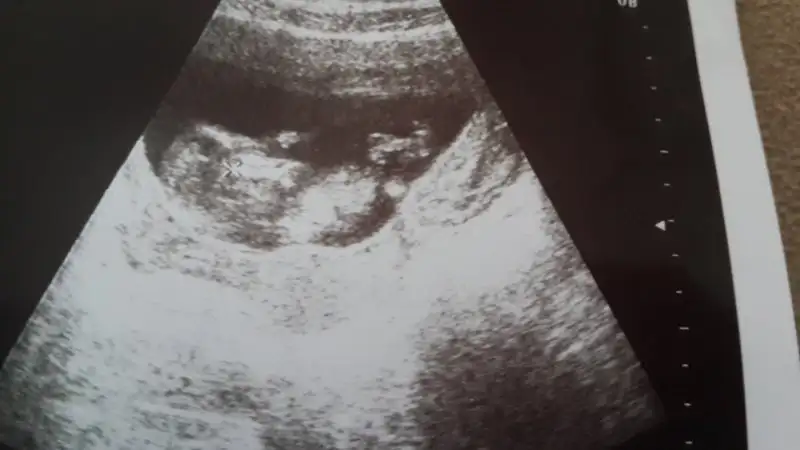

Aslında daha önce sormuştum ama tek bir arkadaş yorum yazdı belki farklı görüşler olur diye tekrar fikir almak istedim :) burda 12+1 iz normalde ama 3 gün önden gidiyoruz 12+4 görünüyor o yüzden minnağım :)

eger o çıkıntı ayak değilse erkek gibi duruyorKIZLAR SİZCE BENİMKİ NE

Kiz canım öyle gozukuyorKIZLAR SİZCE BENİMKİ NE